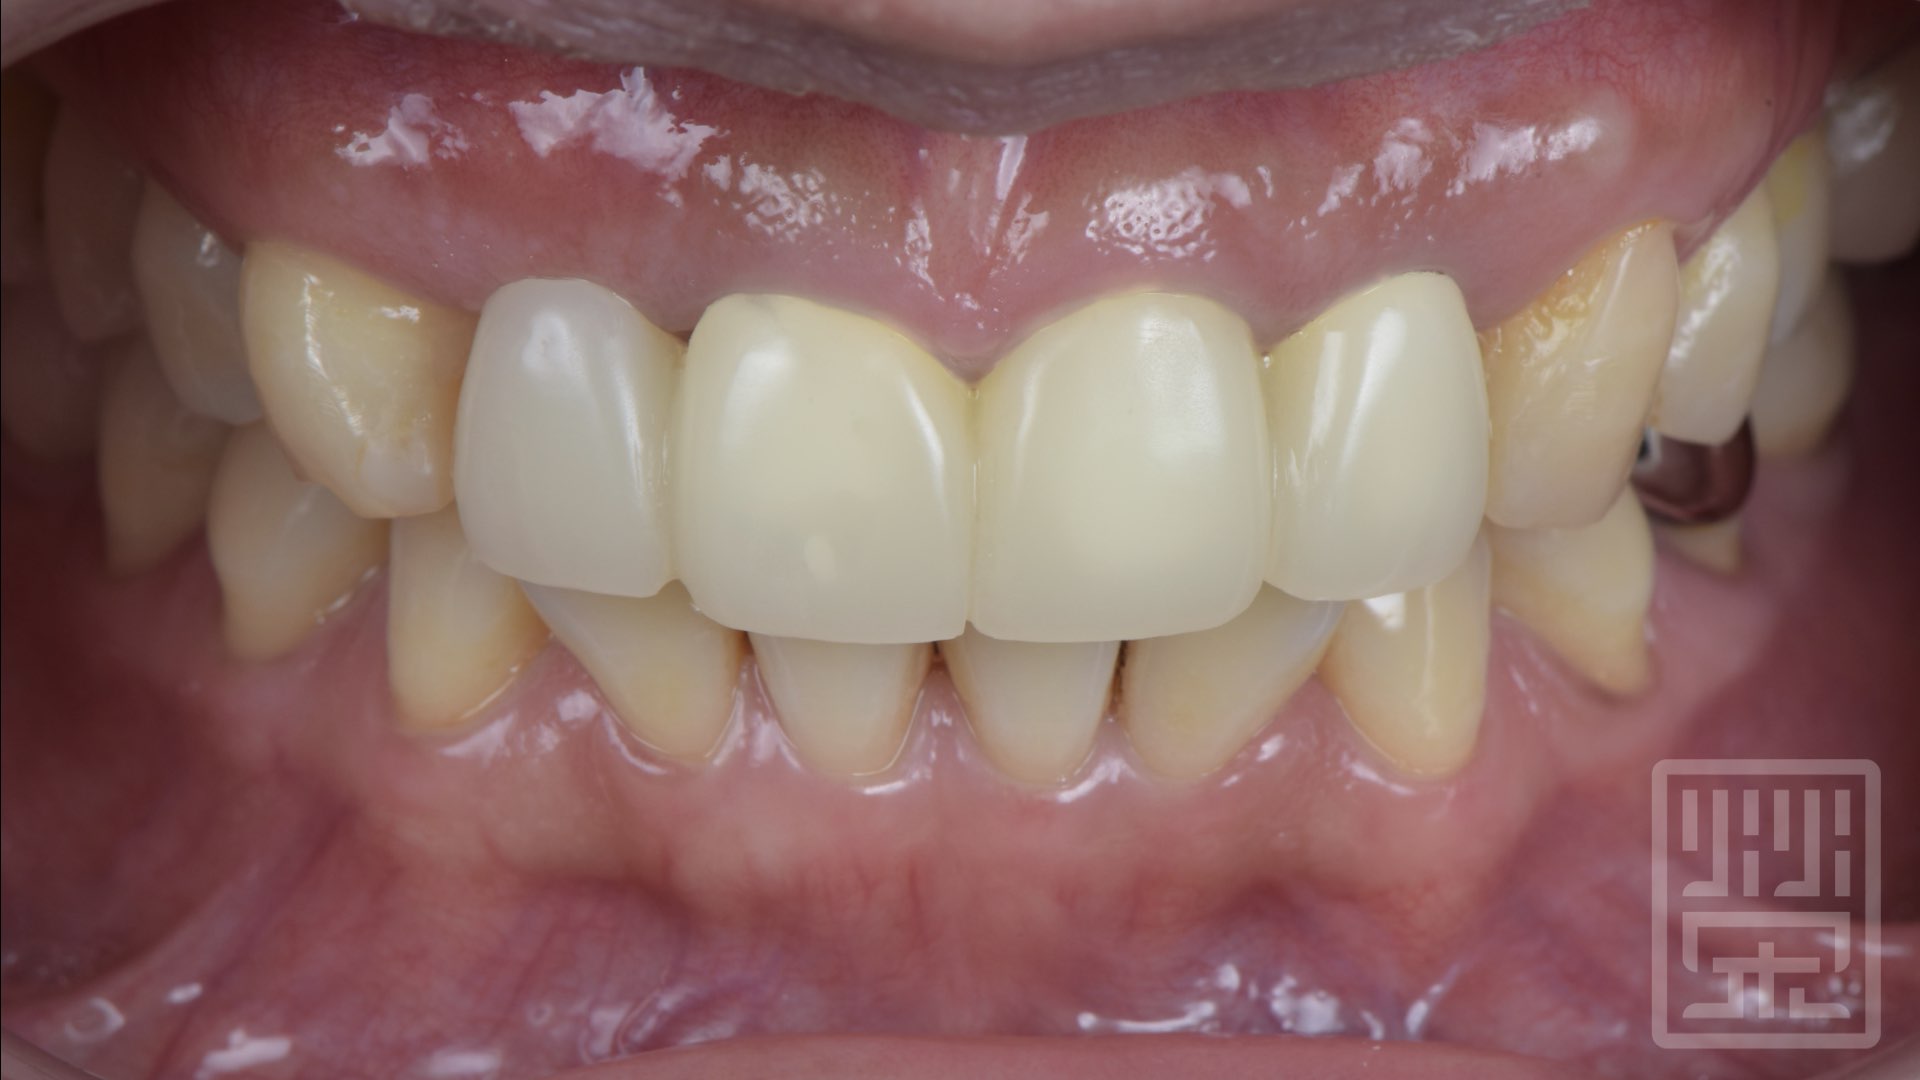

臨時假牙修復